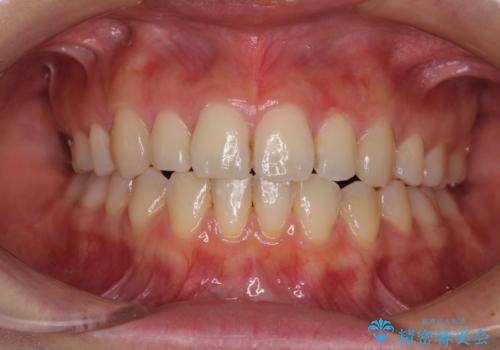

抜歯矯正を行ったことで、デコボコが改善されただけでなく、口元も下がったことで口が閉じやすくなりました。